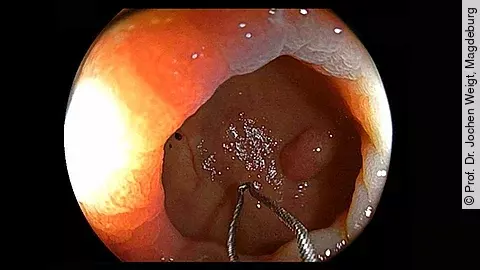

Unser neues Endoskopie-Video zeigt einen offensichtlichen Befund, der aber auch leicht zu übersehen ist. Welcher das ist und welche Methode zur Behandlung angewandt wurde, präsentiert PD Dr. Jochen Weigt vom Uniklinikum Magdeburg.

Das Management der Antikoagulation bei Patienten mit Polypektomie ist immer noch umstritten. Eine japanische Studie konnte jetzt zeigen, dass die „Cold-snare“-Polypektomie (CSP) bei fortlaufender Antikoagluation zur Entfernung von Polypen < 1 cm mindestens genauso sicher ist wie die „Hot-snare“-Polypektomie (HSP) plus Heparin-Bridging (HB).